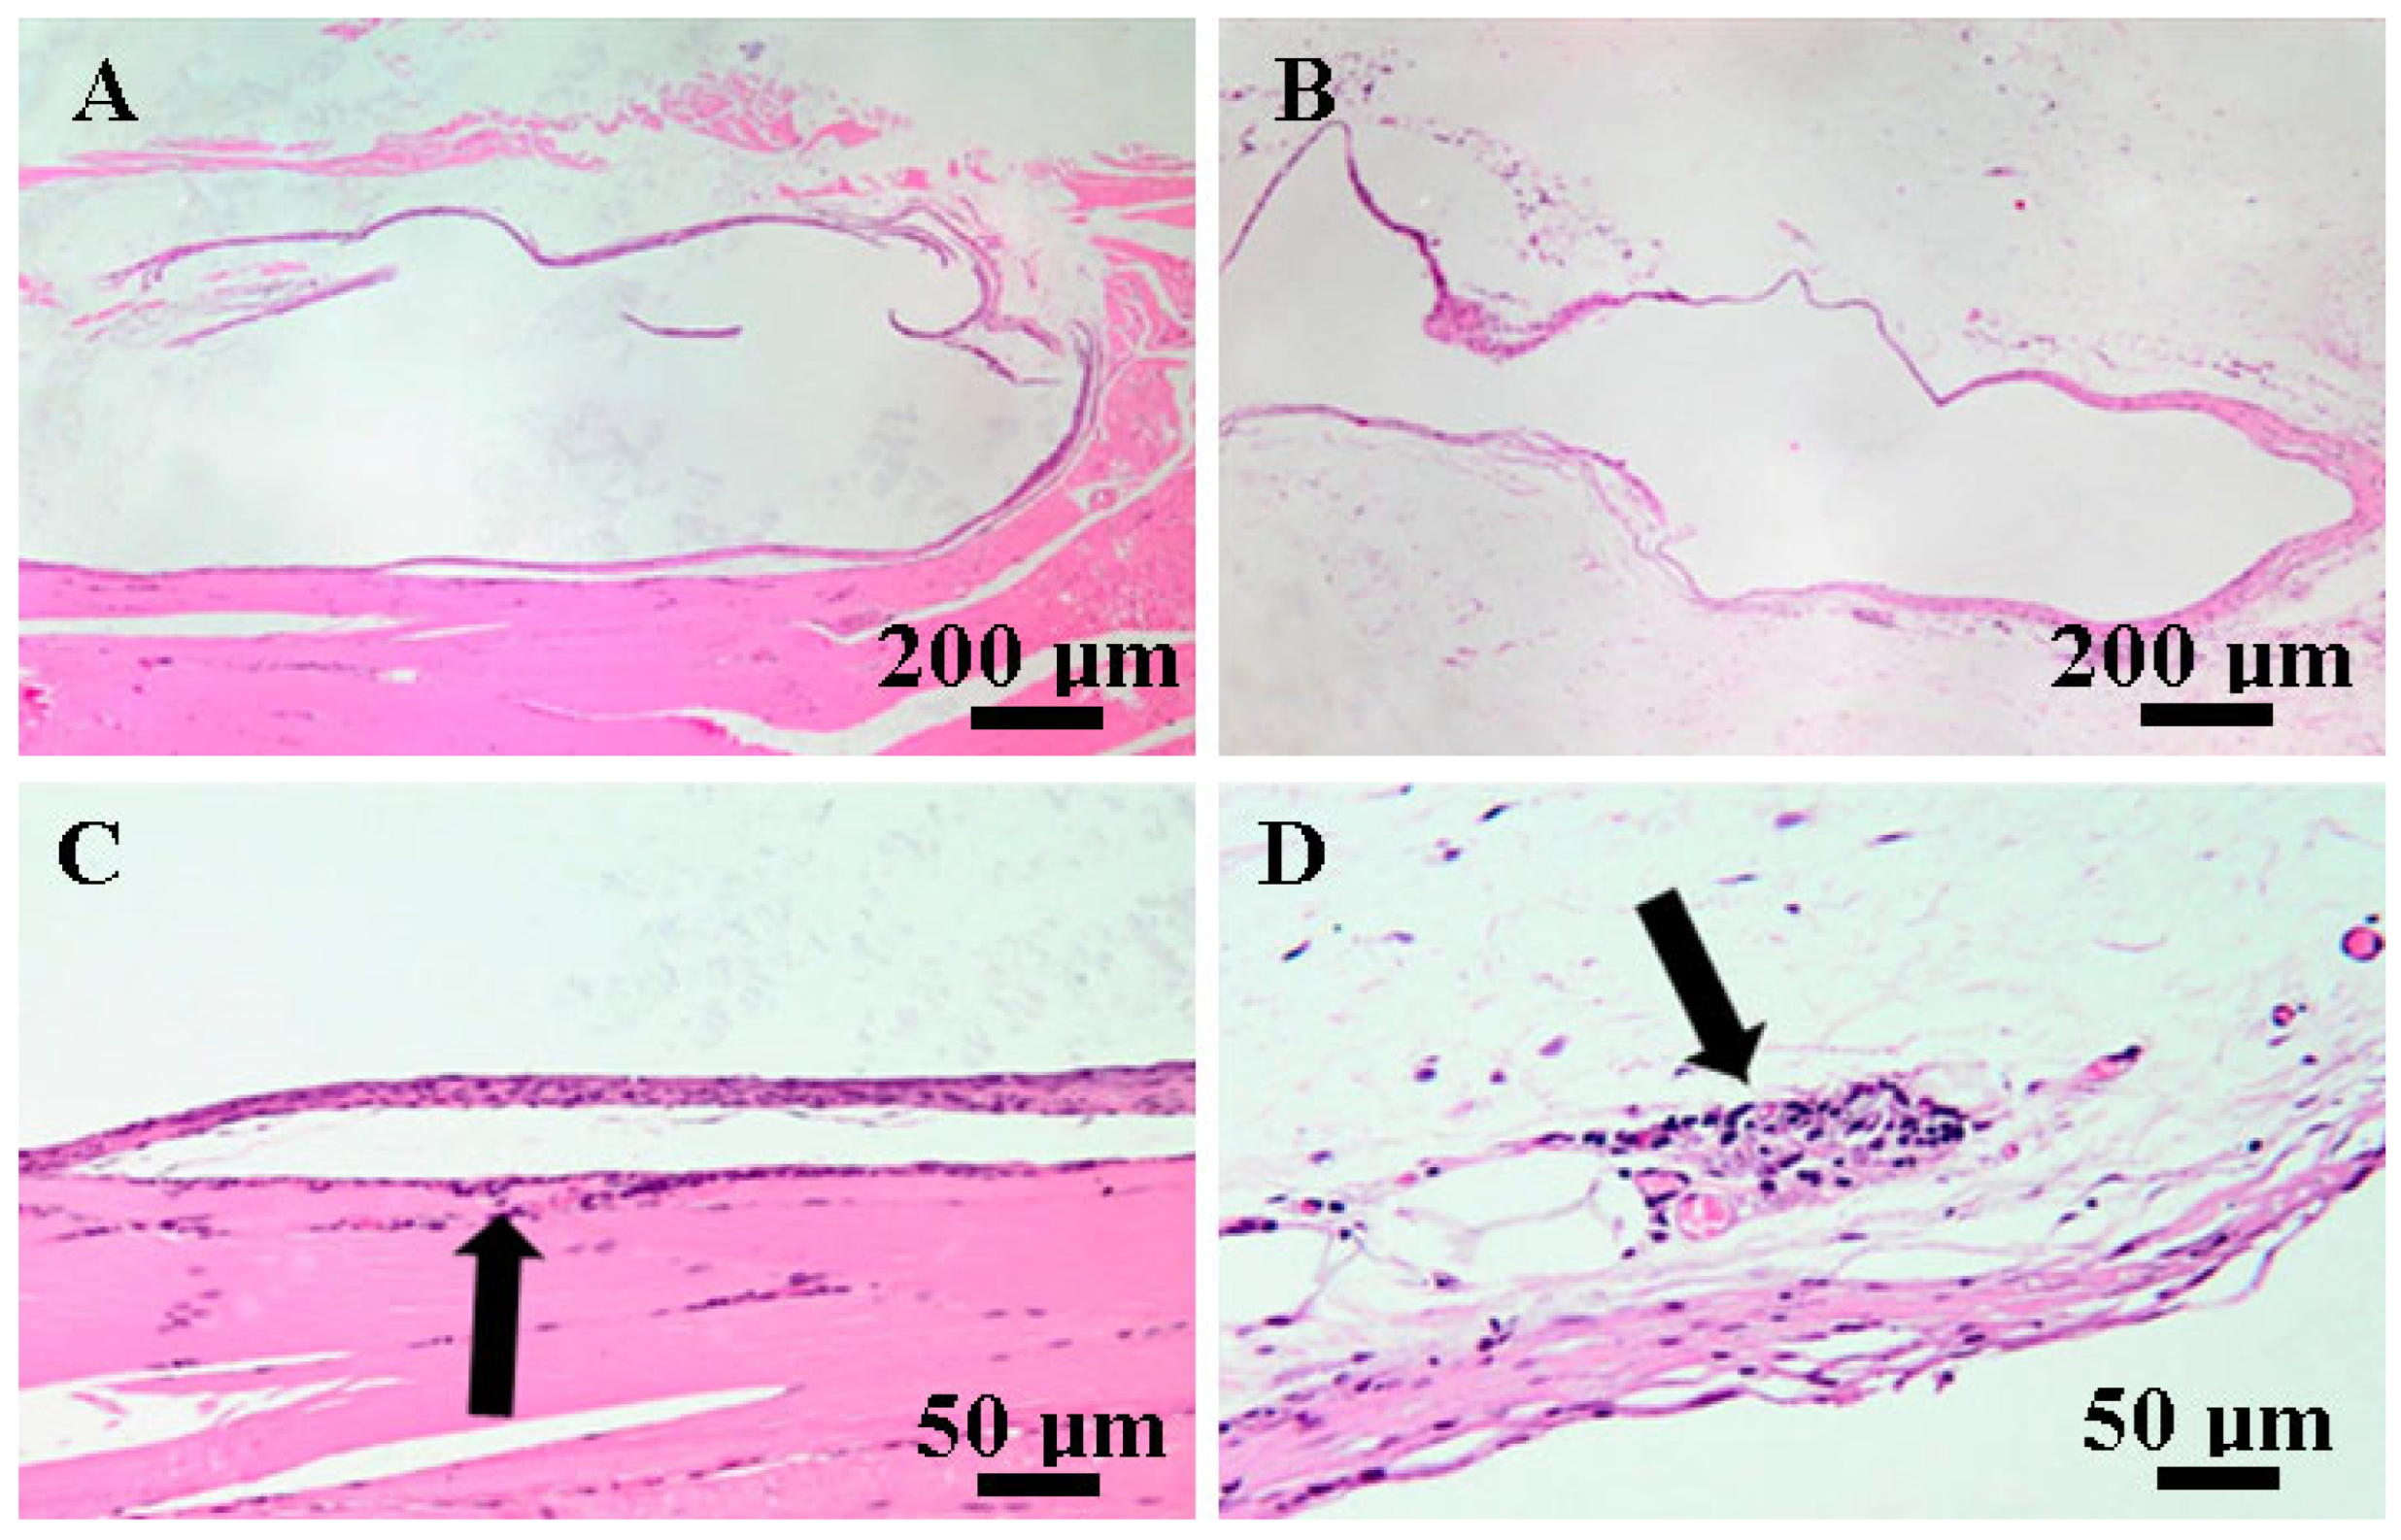

3.5. Histopathological Findings